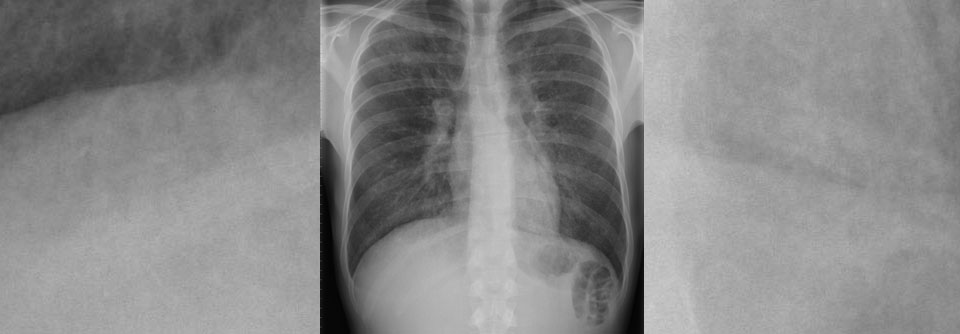

Pneumonieverdacht

Schallen oder röntgen?

Die diagnostische Aussagekraft der CT ist kaum zu überbieten, wenn eine Lungenentzündung vermutet wird. Das Verfahren bietet sich im Alltag jedoch…